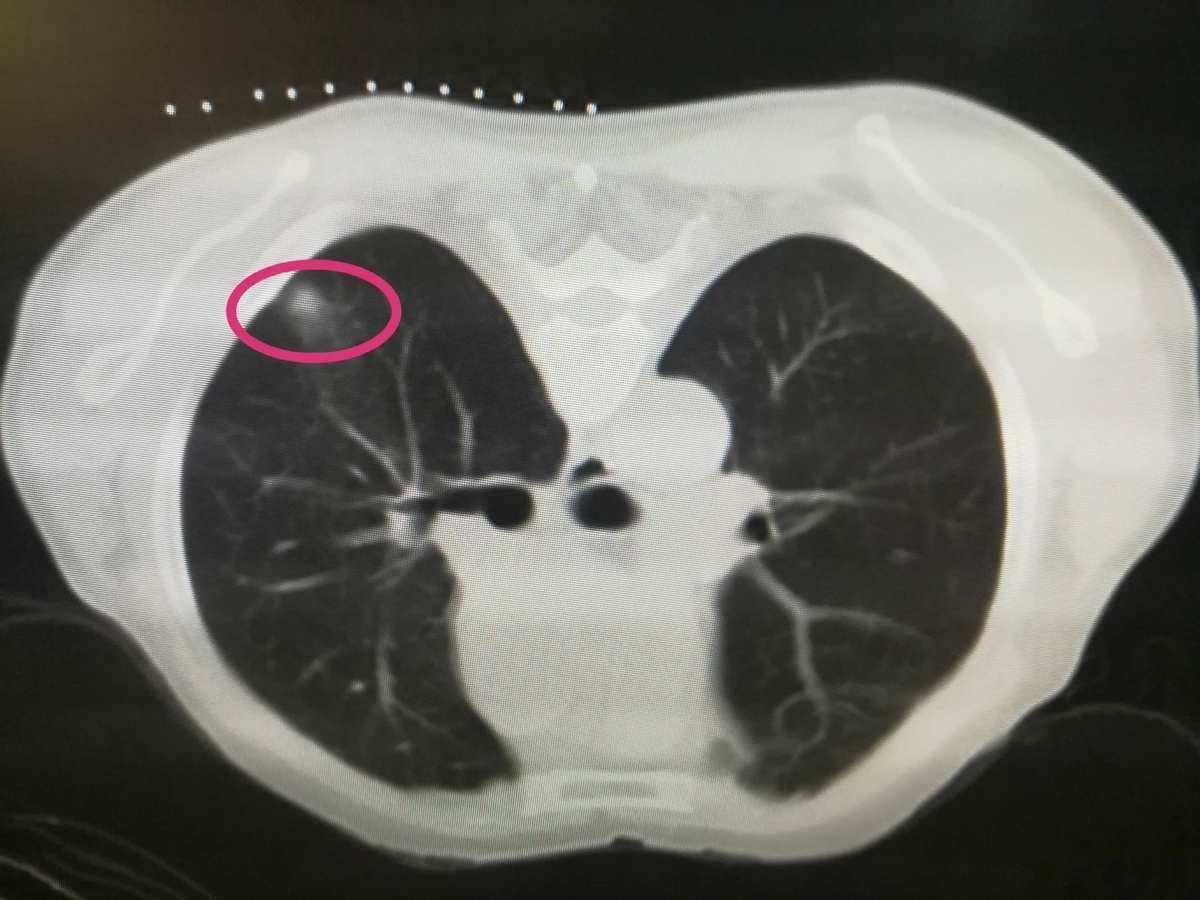

老中医张士舜的肺结节、乳腺结节、甲状腺结节经验方!

主治:结节病。广泛应用于肺结节、乳腺结节、甲状腺结节等。

张士舜根据“三辨论治”中的辨病位论治,肺结节可加入肺形草;